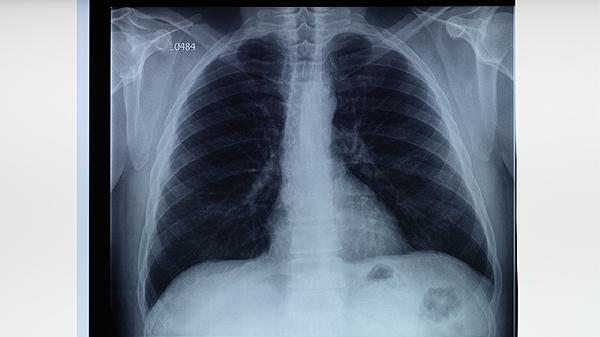

肺结核患者除规范用药外,需保证每日优质蛋白摄入如鸡蛋、鱼肉,补充维生素A/C/D增强呼吸道黏膜修复。注意居住环境通风,避免劳累,定期复查胸部影像学。出现咯血、气促等急症需立即就诊。所有治疗均应在结核病专科医生指导下进行,不可自行调整药物方案。